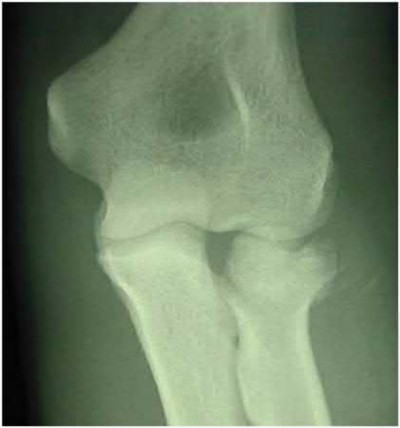

A 22-year-old male falls onto an outstretched hand and sustains a displaced fracture through the proximal pole of the scaphoid. Avascular necrosis of the proximal pole is highly likely due to the disruption of its primary vascular supply. Which vessel provides this critical retrograde perfusion?

Explanation

The primary blood supply to the scaphoid is from the dorsal carpal branch of the radial artery, which enters the dorsal ridge of the scaphoid at the waist and courses proximally. This retrograde blood flow makes proximal pole fractures highly susceptible to avascular necrosis and nonunion. The superficial palmar branch provides a minor supply (about 20%) to the distal pole.